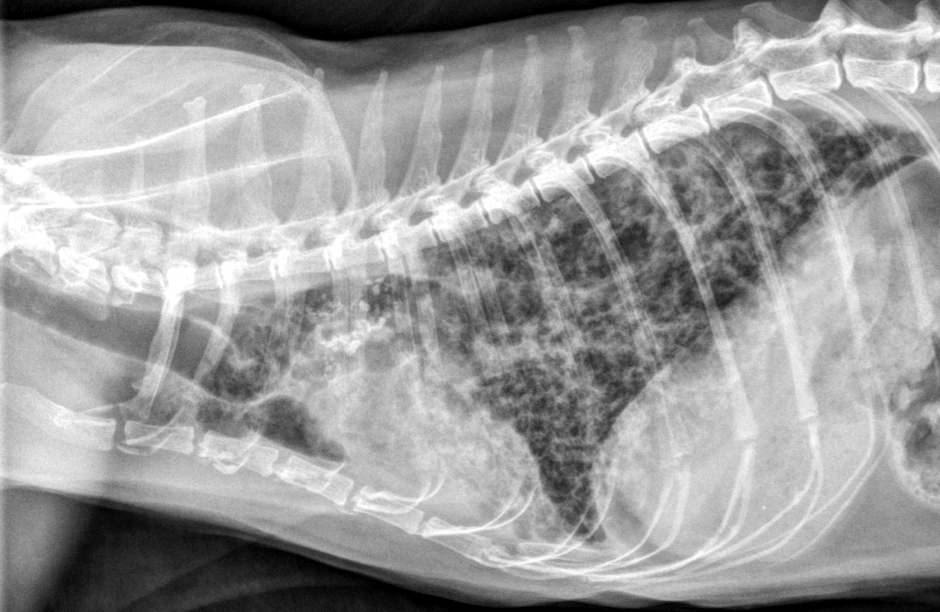

Lung Pattern?

Interstitial *Diffuse, marked*